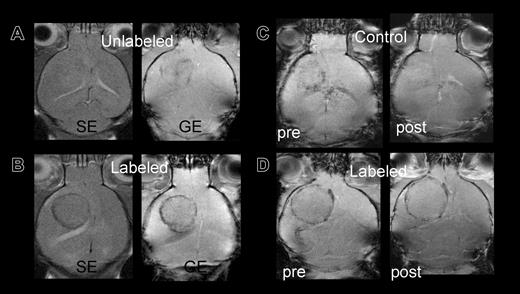

Control mice infused with unlabeled or killed FE-PLL-labeled cells did not develop a hypointense ring surrounding the tumor performed 10 or more days following RT2 cell implantation. Control versus labeled mice are shown in Figure 3A-B. One mouse that received killed labeled cells on day 3 following RT2 cell implantation had slight decrease in signal intensity around the tumor on day 12 after infusion of Sca1+ cells that was thought to be due to blood flow effects. To discriminate the signal intensity decrease because of slow venous blood flow from the susceptibility artifact for FE-PLL-labeled cells, Gd-DTPA was administered. An increase in signal intensity and disappearance of hypointense regions occurred following the infusion of Gd-DTPA in the mouse that received killed labeled Sca1+ cells, whereas the hypointense area remained in a mouse with FE-PLL-labeled viable cells (Figure 3C-D).

Control versus labeled mice: group 3 mice imaged at day 10 after cell transplantation. (A) Signal intensity in tumor of control mouse with unlabeled cells on either spin echo (SE) or gradient echo (GE) sequences are almost isointense with contralateral hemisphere. (B) Mouse receiving FE-PLL-labeled cells demonstrates clear ring at the tumor periphery on both SE and GE. (C-D) Post-Gd-DTPA contrast-enhanced MRIs to differentiate between slow blood flow in patent vessels at the tumors' edge and the presence of magnetically labeled cells. The hypointense area in a group 2 control mouse (C) that received killed labeled cells becomes isointense with surrounding brain after contrast, indicating the Gd-DTPA in the area increased the signal intensity, whereas the dark ring persists in the mouse with labeled cells (D).